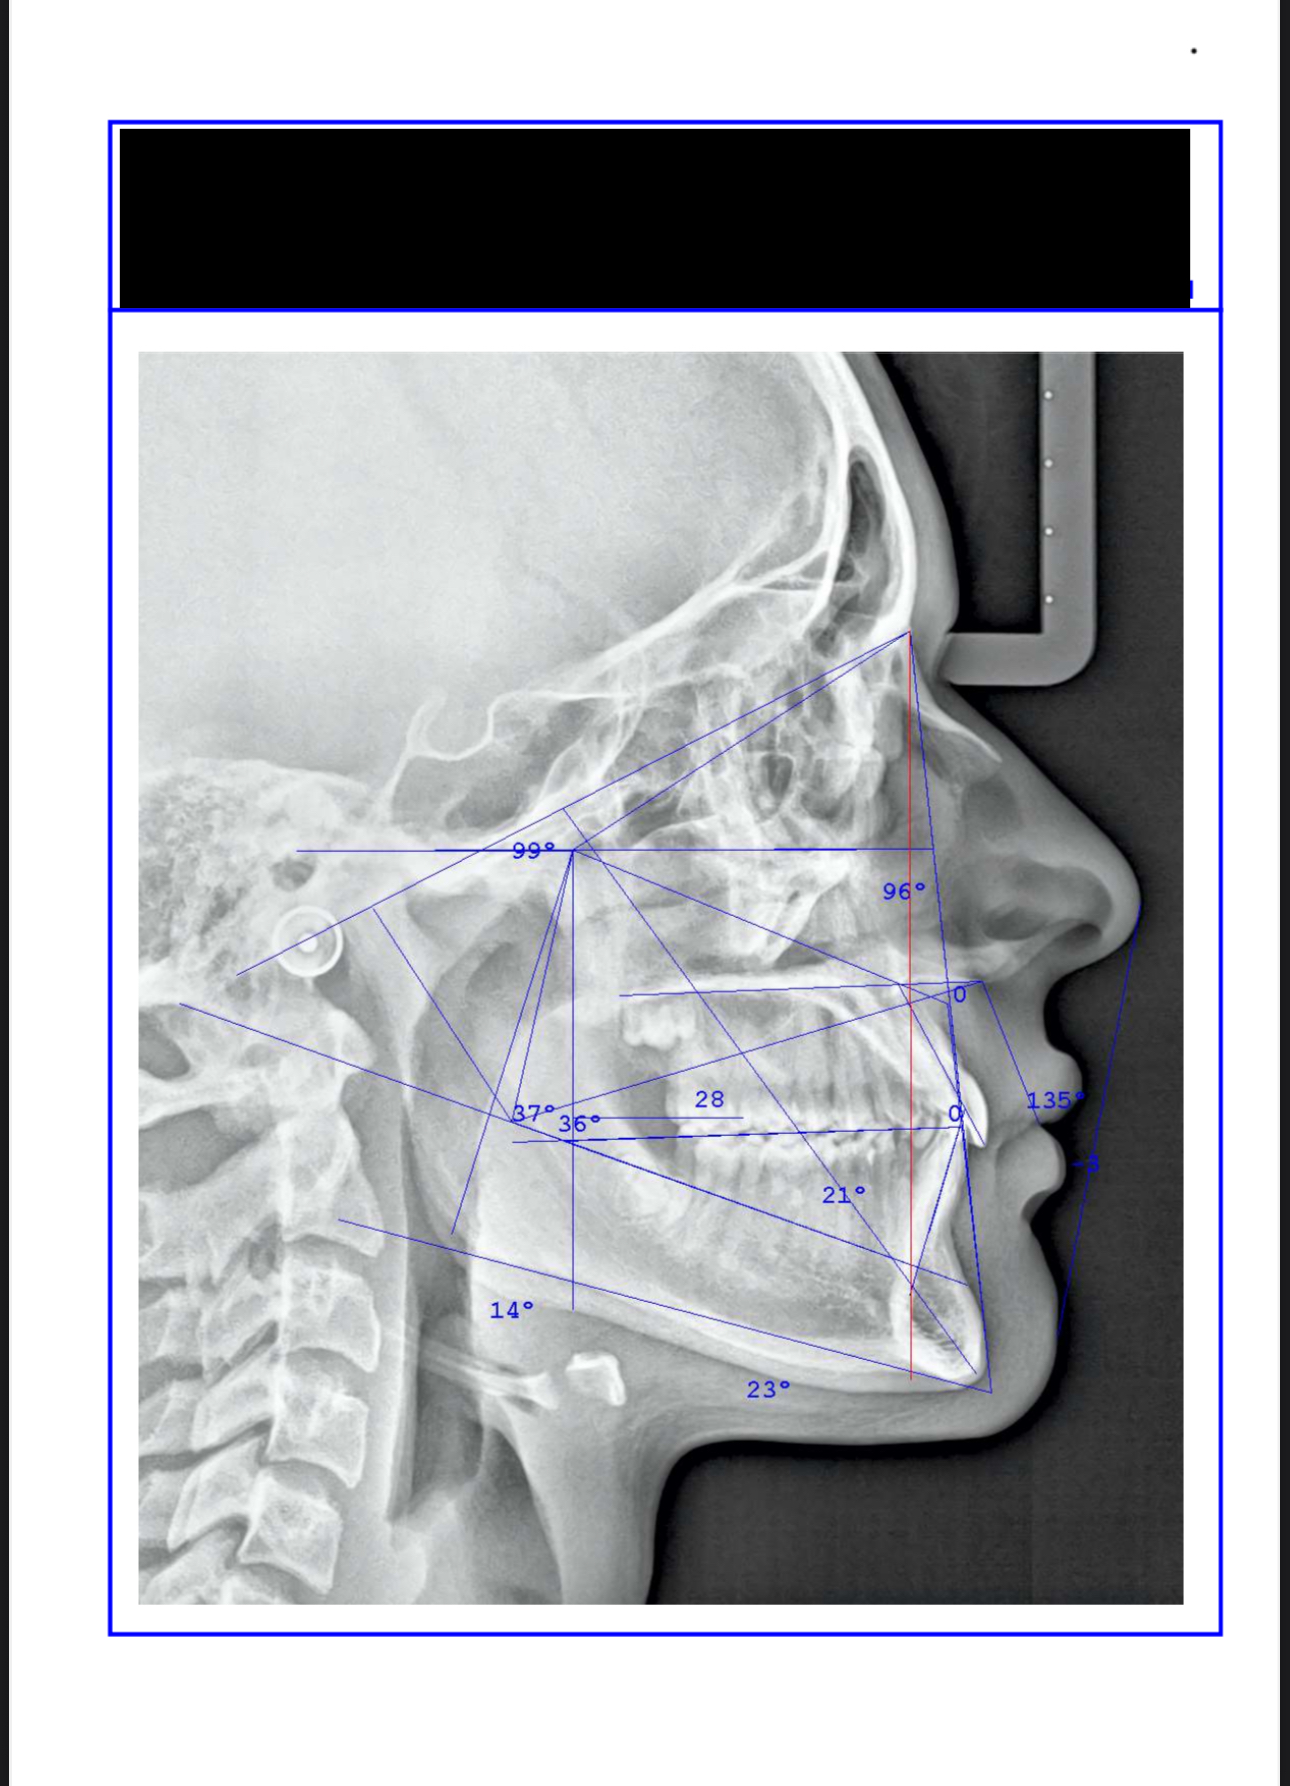

just made a few scans and im considering palete expander of face mask, ideally both?

Rapid Palatal Expander (RPE) + generic face mask